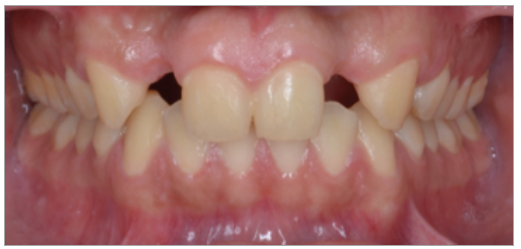

Paciente de sexo masculino de 24 años de edad, de raza mestiza, sin antecedentes sistémicos y oclusalmente estable, que fue transferido al servicio de Rehabilitación Oral del Posgrado y Especialización de la Universidad Peruana Cayetano Heredia, Lima, Perú. Recibió previamente tratamiento ortodóncico en el servicio de Ortodoncia y Ortopedia Maxilar por 6 años. Al examen intraoral presentó agenesia de las piezas 12 y 22 con evidencia de defectos óseos, presenta fenotipo periodontal grueso (figura 1). Al examen radiográfico se observa disminución generalizada de las raíces (Rizomicri), presenta ensanchamiento del ligamento periodontal generalizado (figura 2). Para el plan de trabajo para el diagnóstico se obtuvieron modelos de estudio primario, realizando el encerado para la planificación del tratamiento del sector anterosuperior. Al análisis tomográfico se evidenció poca disponibilidad ósea, motivo por el cual se planificó dos injertos en bloque de mentón con hueso particulado y plasma rico en plaquetas previo a la colocación de implantes dentales (figura 3 y figura 4). Pasado el tiempo de osteointegración (6 meses) se colocaron dos implantes Strong WS Cono Morse (SIN®, Sao Paulo, Brasil) de 3.5 mm x 11 mm. En la segunda fase, se confeccionaron provisionales de acrilico termocurado Vitalloy® (Vitacryl; A. Tarrillo Barba S.A., Lima, Perú) para el manejo de los tejidos blandos a nivel de las piezas 12 y 22, los cuales estuvieron fijados a un cilindro provisional de titanio (SIN®, Sao Paulo, Brasil) atornillado al implante, verificando la adaptación de este al implante mediante una radiografía periapical (figura 5). El cilindro fue recortado dando una altura de 6 mm, los provisionales fueron agujerados en el medio (figura 6), de tal forma que el cilindro calce en el medio del espacio edéntulo, se cubrió la entrada del cilindro con teflón (Golfo USA®) y se capturó el cilindro con acrílico de autocurado Duralay color 62 (Reliance Dental Manufacturing LLC, Illinois USA) (figura 7). Después del acrilizado se retiró el provisional, en la parte cervical se realizó un incrementó con resina fluida (Filtek™ Z350XT Flow - 3M ESPE Dental Products. St. Paul, Minnesota, USA) formando el contorno crítico a 2mm por debajo del zenit de los incisivos centrales de tal manera que entre los zenits de los incisivos centrales, laterales y caninos formen una zona triangular. El contorno subcrítico se realizó de forma convexa (figura 7 y figura 8). Se finalizó con el acabado y pulido del provisional con gomas de grano grueso (gris) y grano fino (verde) (Politip, Ivoclar-Vivadent; Schaan, Liechtenstein). Se manejó la conformación de los tejidos blandos en 2 citas mediante la adición por capas de resina compuesta (Filtek™ Z350 - 3M ESPE Dental Products. St. Paul, Minnesota, USA) a nivel del contorno crítico y subcrítico a las 2 semanas y 4 semanas de la instalación del provisional (figura 9 y figura 10). Se logró conformar las papilas interdentales, el contorno crítico y subcrítico observando que los tejidos se encontraran estables, sin inflamación, con el color de la encía igual a la encía adyacente; todo esto nos indicó que se podía realizar la impresión definitiva. La instalación final se realizó con coronas metal cerámicas cementadas (figura 11 y figura 12).